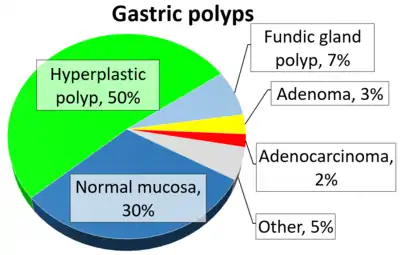

Incidences and malignancy risks of various types of colorectal polyps[2] Relative incidences of gastric polyps[3]

Relative incidences of gastric polyps[3]

- ↑ García-Alonso, Francisco Javier; Martín-Mateos, Rosa María; González-Martín, Juan Ángel; Foruny, José Ramón; Vázquez-Sequeiros, Enrique; Boixeda de Miquel, Daniel (2011). "Gastric polyps: analysis of endoscopic and histological features in our center". Revista Española de Enfermedades Digestivas. 103 (8): 416–420. doi:10.4321/S1130-01082011000800005. ISSN 1130-0108. PMID 21867351.